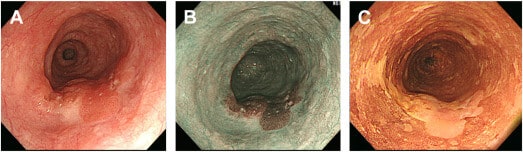

Esôfago de Barrett

O esôfago de Barrett (BE) caracteriza-se pela substituição do epitélio escamoso normal por epitélio colunar especializado com células caliciformes, geralmente identificado endoscopicamente como mucosa de coloração salmão proximal à junção gastroesofágica (GEJ). Além disso, classifica-se com base no comprimento do segmento em segmento curto (<3 cm) e segmento longo (≥3 cm).

Durante a endoscopia, recomenda-se o uso de biópsias sistemáticas em múltiplos pontos do segmento suspeito, de acordo com o comprimento do BE, para detecção de displasia.

Lesões visíveis ou áreas de mucosa irregular podem indicar displasia de baixo e alto grau ou carcinoma intramucoso. Endoscopicamente, essas áreas podem apresentar elevações, nódulos ou alterações na textura e na vascularização da mucosa, sugerindo transformação neoplásica.

Nesse contexto, técnicas avançadas como endoscopia de alta definição, cromoendoscopia, NBI e inteligência artificial (IA) auxiliam na detecção e caracterização dessas alterações, com alta sensibilidade e especificidade.